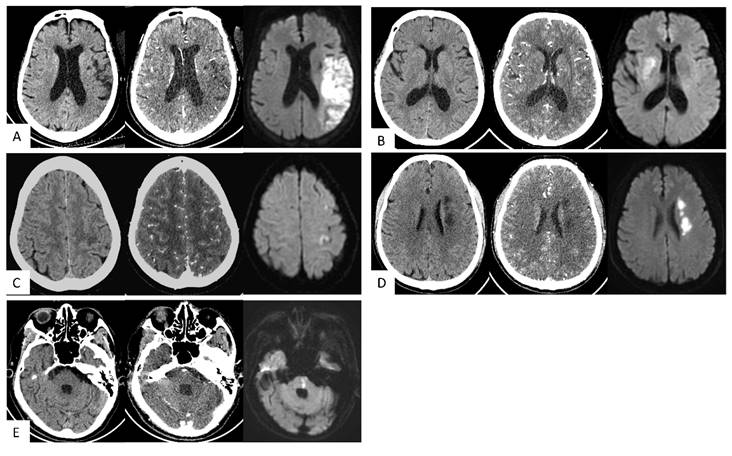

Diagnostic accuracy of three image models across different area subtypes of AIS

NCCT+CTA-SI showed superior lesion detection rate compared to NCCT or CTA-SI models (all p<0.05). For LTI, the lesion detection rate of NCCT+CTA-SI was higher than NCCT (p<0.05); for DPI, the lesion detection rate of NCCT+CTA-SI was higher than the CTA-SI model (p<0.05). For the other three subtypes, no statistical significance was observed among the 3 models (Table 3). Typical case images are shown in Figure 3A-E.

Figure 3

Typical cases. (A) Large vessel trunk infarction (LTI). An 85-year-old female; onset time 3+ hours. NCCT showed no obvious abnormalities. CT angiography source images (CTA-SI) revealed a large, slightly low attenuation in the left frontal and parietal lobes. The combination of CTA-SI and NCCT depicted left frontal and parietal lobe ischemic stroke. Diffusion-weighted imaging (DWI) showed a large, diffuse, restricted area in the left frontal and parietal lobes. (B) Deep perforator vessel infarction (DPI). A 67-year-old female; onset time 23 hours. NCCT showed no obvious abnormalities. CTA-SI revealed a slightly low attenuation in the right basal ganglia. The combination of CTA-SI and NCCT depicted right basal ganglia ischemic stroke. DWI showed a patchy diffuse restricted area in the right basal ganglia. (C) Superficial perforator vessel infarction (SPI). A 67-year-old female; onset time 24 hours. NCCT showed a slightly low attenuation in the subcortical region of the left parietal lobe. CTA-SI showed no obvious abnormalities. The combination of CTA-SI and NCCT did not indicate the infarct focus. DWI showed a patchy and punctate restricted area in the subcortical region of the left frontal and parietal lobe. (D) Watershed infarction (WI). A 61-year-old male; onset time 3+ hours. NCCT and CTA-SI demonstrated chainlike low attenuation in the left paraventricular region, and there were no signs of old lesions in the surrounding area. DWI showed a chainlike restricted area in the left paraventricular region. (E) Infratentorial infarction (IF). A 78-year-old male; onset time 1+ hours. NCCT and CTA-SI showed no obvious abnormalities in the posterior fossa. Beam hardening artifacts were shown on CTA-SI. DWI showed patchy restricted area in the pons which located in the posterior fossa.